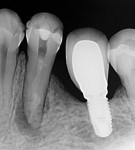

A 50-year-old woman was referred for the endodontic treatment of her mandibular left second bicuspid. The patient was suffering from pain and presented with swelling and a sinus tract. During the radiographic exam, the presence of root resorption and a periapical lesion could be observed (Figure 5). The canal was instrumented using a series of rotary NiTi files (Bassi Logic Shaping & Glidepath Files, Bassi Endo) up to size 50/.01 and then copiously irrigated with a 2.5 % NaOCl solution. Next, a 17% EDTA solution was used, and then the canal was filled with calcium hydroxide, which would remain in place as an intracanal medication for 15 days (Figure 6).

At the following appointment, the calcium hydroxide was removed, and the canal was irrigated using the same protocol that was used in case No. 1. First, 3 mL of 2.5% NaOCl solution was placed and agitated for 60 seconds at 20,000 rpm with the plastic activating file. Then, 1 mL of 17% EDTA solution was agitated for 60 seconds at 20,000 rpm, followed by 3 mL of 2.5% NaOCl solution that was agitated for 60 seconds at 20,000 rpm, and a final irrigation with 1 mL of saline solution. After irrigation, the canal was properly dried with absorbent paper cones. The tooth was then filled with the bioceramic root canal sealer (BIO-C® Sealer, Angelus) and gutta-percha using a lateral condensation technique associated with the use of the McSpadden condenser (ie, Tagger's hybrid technique) (Figure 7).11 The final restoration was performed with composite resin. At the 3-month (Figure 8) and 18-month (Figure 9) follow-up visits, healing of the periapical tissue was observed, and the patient was completely asymptomatic.